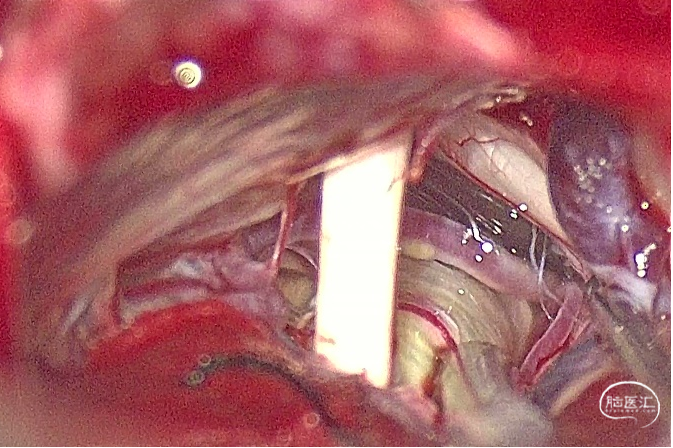

手术过程照片:

手术过程照片: